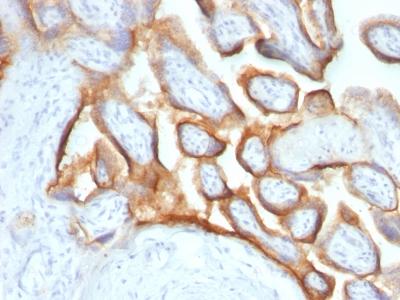

Formalin-fixed, paraffin-embedded human Placenta stained with hCG alpha Monoclonal Antibody (SPM552).

Immunohistochemistry (Formalin-fixed) (1-2ug/ml for 30 minutes at RT)(Staining of formalin-fixed tissues requires heating tissue sections in 10mM Tris with 1mM EDTA, pH 9.0, for 45 min at 95°C followed by cooling at RT for 20 minutes);